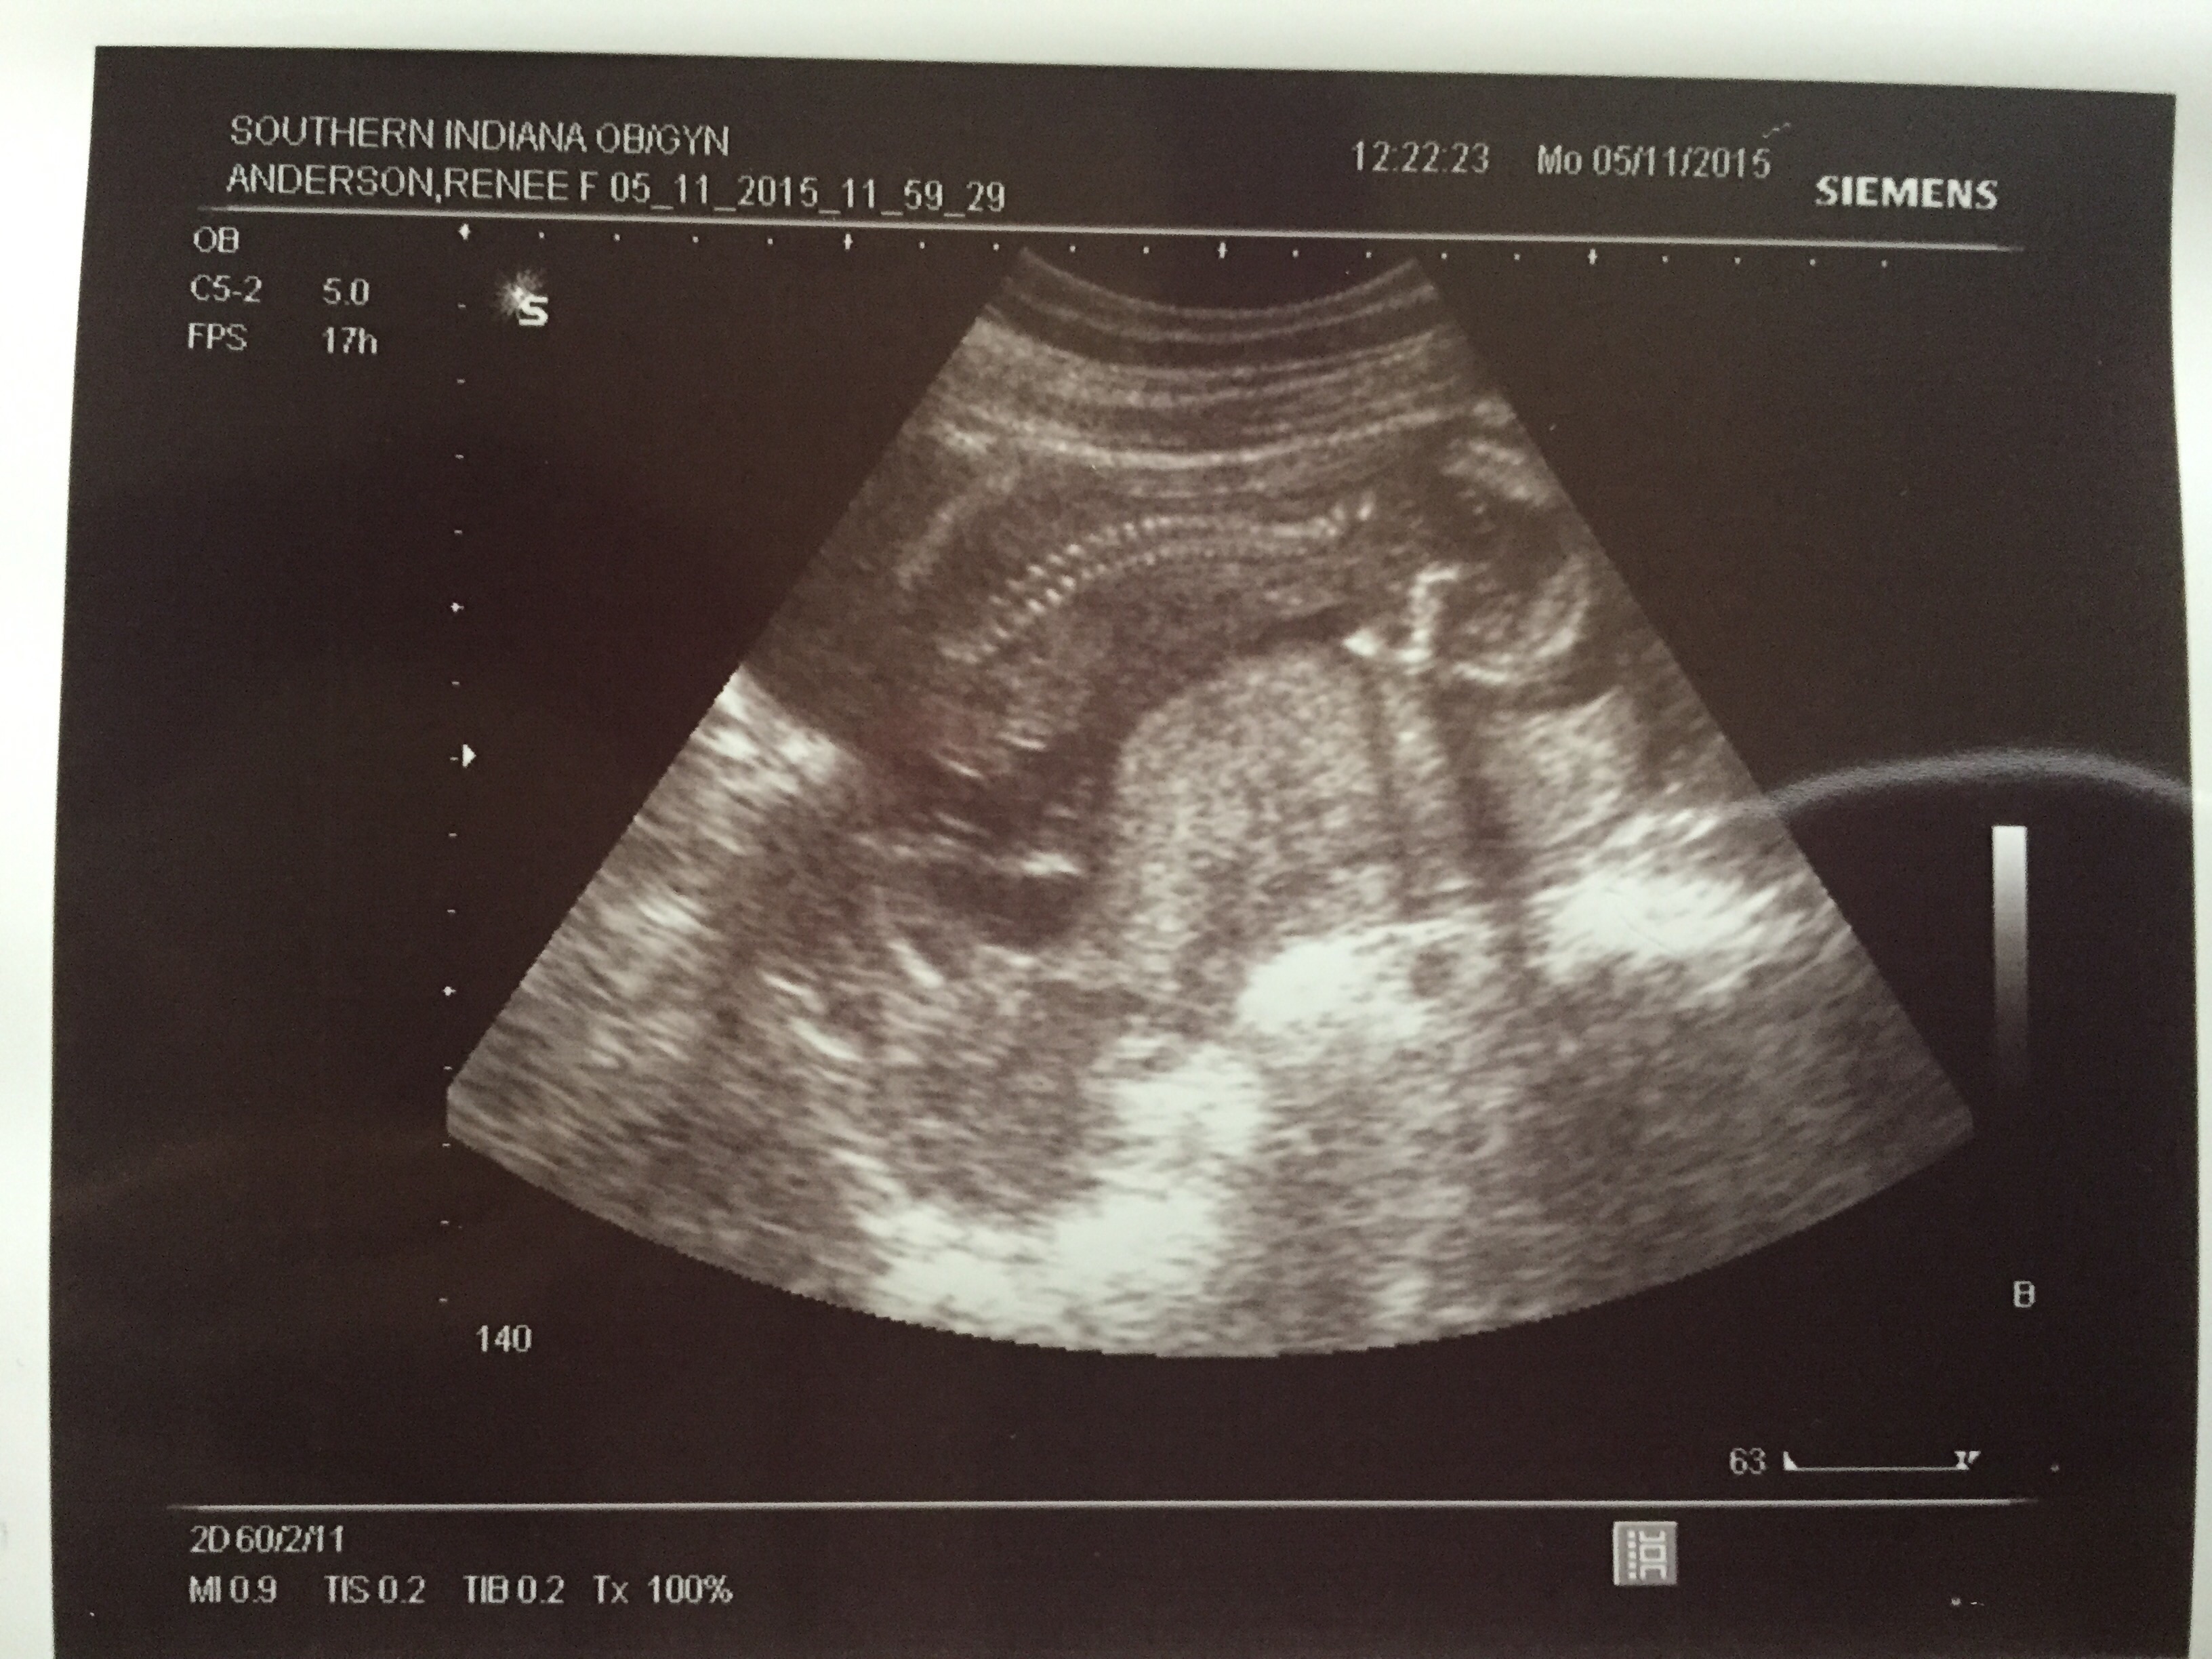

We had a scan on the 11th for a large cyst on my ovary was 13w 1d and husband asked about gender she said super early but could let us know what she thought it might be this is what she showed us.... husband is set that it is was it show but I feel it's super early and that's really really big since it shows half the size of its thigh (see profile pic it won't let me post)

This was last Saturday at 12w3d. My best friend is a sonographer so she got me in. She wanted to try and guess if baby is a boy or girl. When we go by the nub theory it's a boy! She said she's pretty confident. When she was pregnant She knew she was having a girl this early so we will see if she's right!!